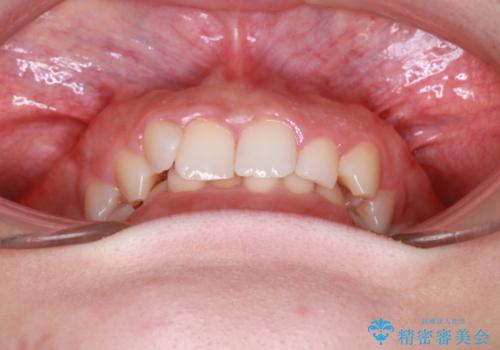

インビザラインで整える深い噛み合わせ

- 患者様は、ディープバイト(深い噛み合わせ)と、咬合平面の左下がりが気になるとのことでご来院されました。診断の結果、非抜歯で治療可能と判断し、透明なマウスピース型矯正装置「インビザライン」を用いる方針としました。治療では、歯列全体の調整を行いながら、咬合平面の水平化を重点的に進める計画を立案しました。2年間で計画的にマウスピースを交換し、左右のバランスと噛み合わせの改善を目指しました。

ディープバイトの矯正は、噛み合わせが深くなりがちなため、細心の注意を払いながら進める必要があります。本症例では、奥歯の高さを調整しつつ前歯の噛み合わせを浅くすることで、全体の咬合バランスを整えました。また、咬合平面の左下がりを修正する過程で、歯列に不均等な力がかからないよう、インビザラインのアタッチメント配置を最適化しました。患者様には装着時間を守っていただき、治療が計画通り進むよう協力をお願いしました。治療終了後には、リテーナーを装着して安定性を確保しました。